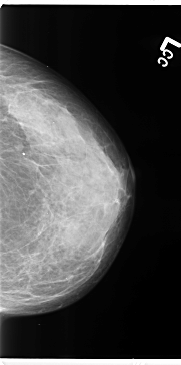

B_3119_1.LEFT_MLO

B_3119_1.LEFT_CC

LEFT_MLO LINES 4696 PIXELS_PER_LINE 2696 BITS_PER_PIXEL 12 RESOLUTION 50 NON_OVERLAY